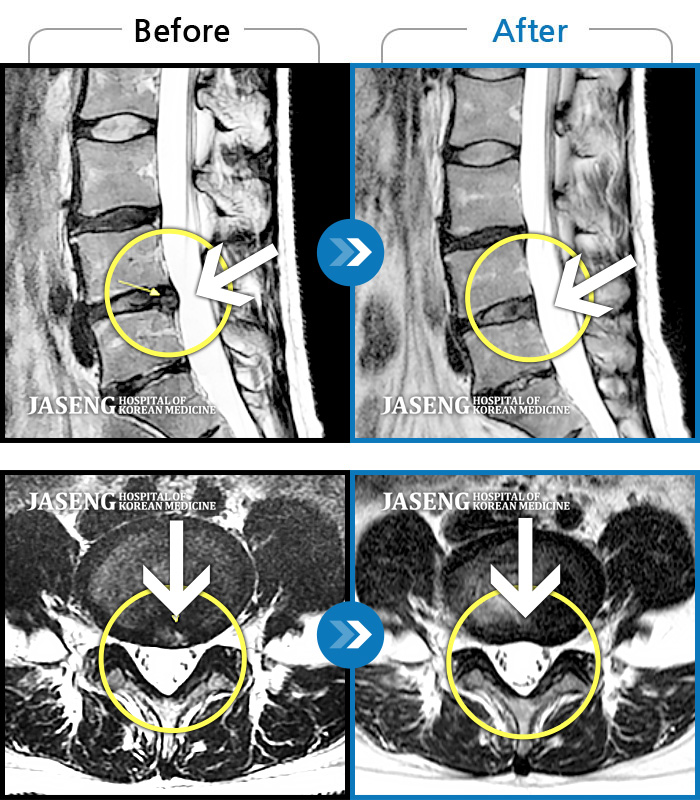

Before

After

허리통증, 왼쪽 다리 저림 및 통증

2018.01.18 ~ 2019.08.09